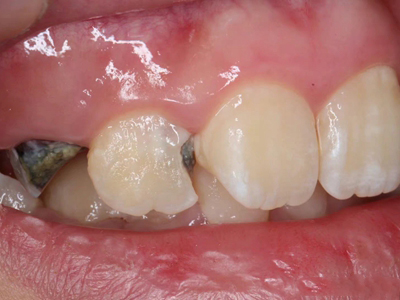

年轻恒牙龋指的是儿童萌出不久的第一恒磨牙龋病和上颌恒切牙龋病,其中第一恒磨牙龋病占年轻恒牙龋的90%,发病早,进展快,可表现为白垩色斑片、点隙窝沟墨浸状龋坏或龋洞。本病的发生和年轻恒牙的特点以及儿童饮食、口腔卫生等因素有关。

年轻恒牙龋好发于第一、二恒磨牙(牙合)面、邻面,上颌中切牙邻面,多为急性龋,龋坏进展快。平滑面的早期龋多为白垩色的斑片,点隙窝沟的早期龋多为浸墨状,表面粗糙。如果早期龋不及时治疗,可逐渐形成大而深的龋洞,易导致牙髓炎和根尖周炎。